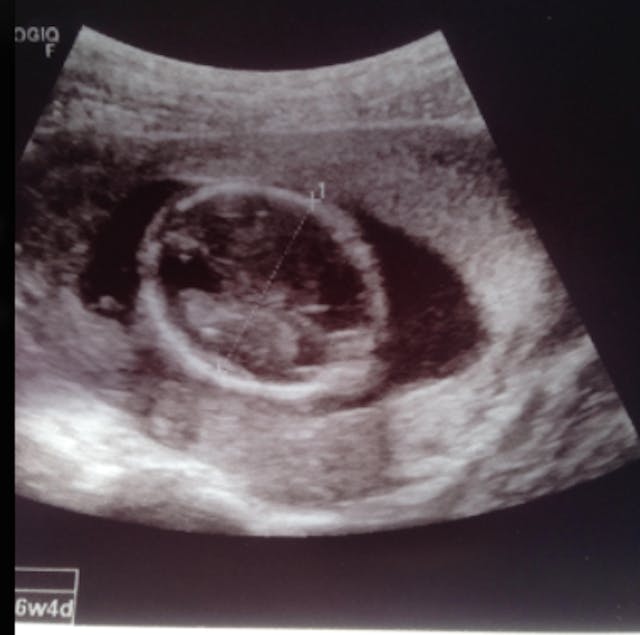

Below is the picture that the mobile unit printed out and gave Amara. You can clearly see the head, body, arm and hand of Amara’s preborn baby.

Amara came out of the mobile unit with a big smile on her face. She showed Whitehead the picture of her baby, exclaiming: “I can’t believe it! Look! It’s a whole baby!”

Before pro-lifers showed her the truth, Amara had no idea her baby was fully developed. Planned Parenthood had led her to believe her 16 week old child was just a circular blob of tissue.